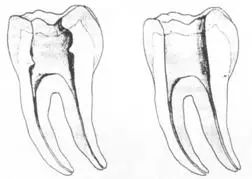

二、根管预备后形态

常规概念的根管预备后形态有:( 1 )便宜形态( convenience form )。( 2 )保持形态( retention form )。

常规概念的根管预备后形态有:

( 1 )便宜形态( convenience form )。( 2 )保持形态( retention form )

( 3 )抵抗形态( resistance form )。

1. 便宜形态

便宜形态是自切端或咬颌面朝向根尖的直线开扩尖锥形态,减少污染物推出根尖孔,方便冲洗、根管充填和侧壁施压。

2. 保持形态

保持形态是根尖狭窄部内 1 — 2mm 的一段距离,由扩大器回转切割而不贴根管壁提拉切割制成,是扩大器的原始形态(近似平行)。在测试主牙胶尖时给测试者有一个牵引抵抗 (tugback) 的感觉。

3. 抵抗形态

抵抗形态是根管预备的根尖形态,它是由扩大器或根管锉尖端 75 度角自然切割而成。其目的是防止根管充填材超出根尖孔,并且使根尖封闭更加严密。